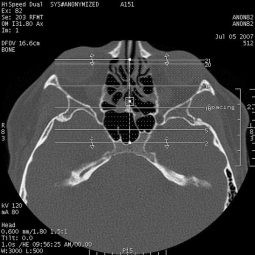

Clínica de Radiología y Ultrasonografía Sosa - Guevara

TAC de senos paranasales

Clinicas > Radiologia

VER GALERÍA